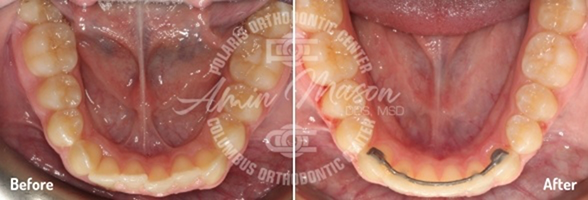

Case 1

Following teenage female patient visited our office with the chief complaint of “crooked teeth.” The patient expressed not being happy with her smile and was not eager to smile. They presented with mild class 2 occlusion, crowding of arches, and crossbite of maxillary lateral incisor teeth. The patient did not wish to have braces and requested clear aligners. She was treated with Invisalign clear aligners and elastics. Total treatment time was 26 months. Patient achieved excellent results.